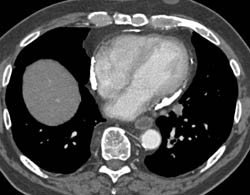

Calcific Pericarditis- Impressive Pericardial Calcification